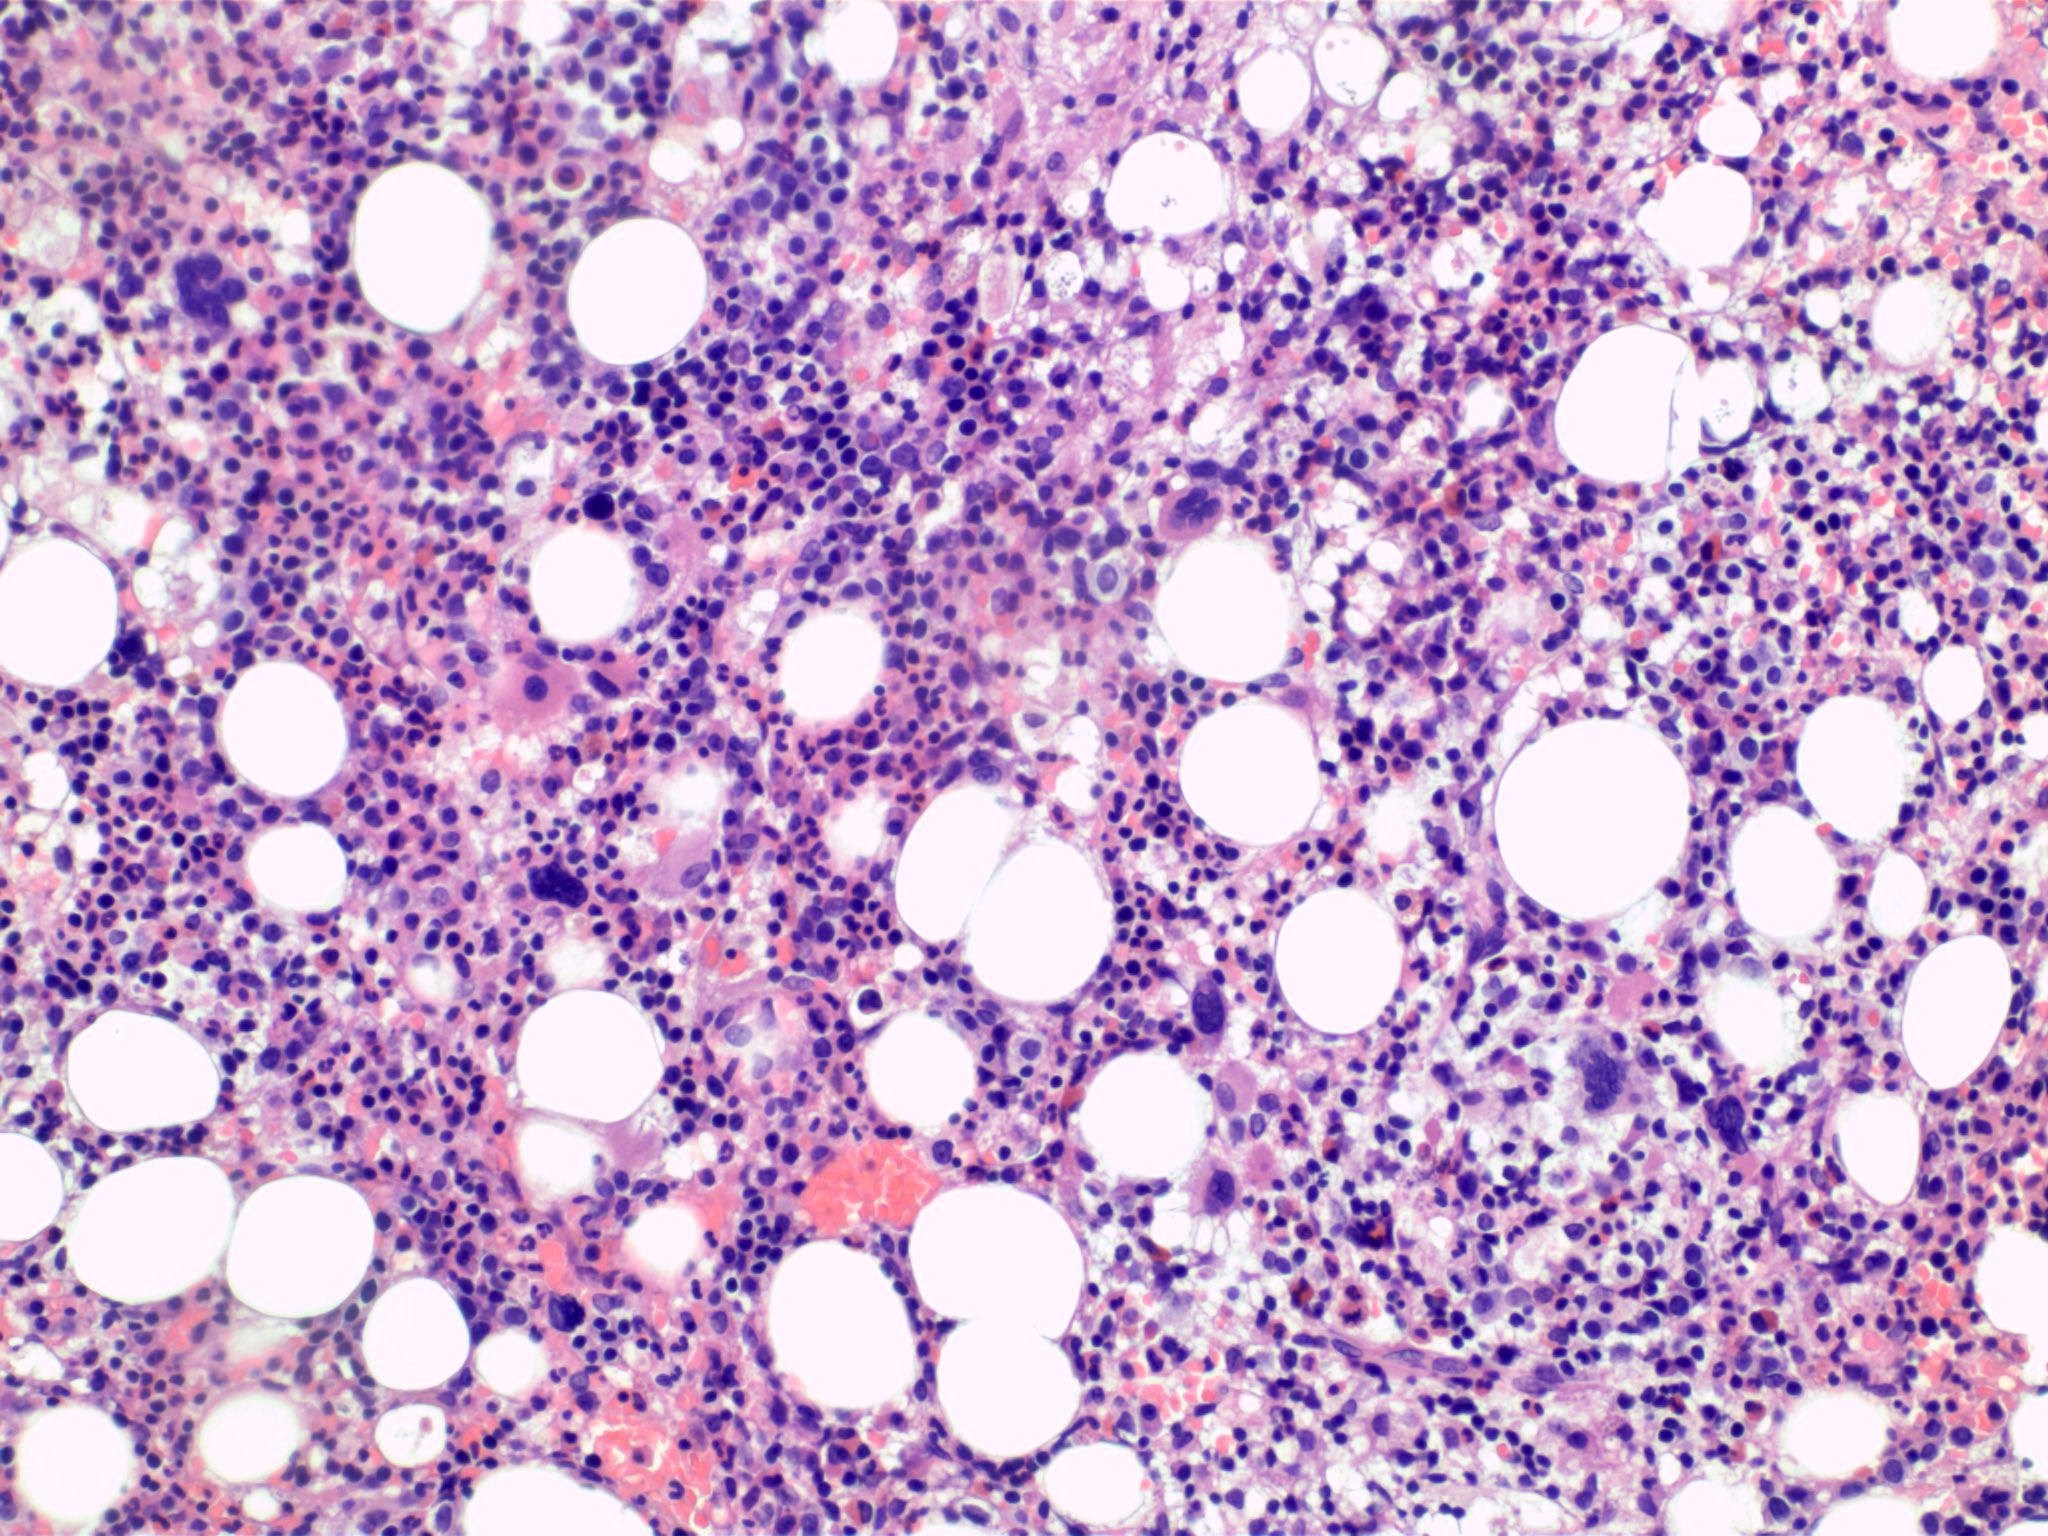

Microscopic (histologic) description

- Bone marrow (Front Oncol 2021;11:778741)

- Hypercellular or hypocellular

- Hypercellular with myeloid lineage predominance

- Dysplasia is seen in at least one hematopoietic lineage

- Bone marrow fibrosis is seen in up to 30%

- Increased megakaryocytes with variable clustering

- Often myelodysplasia-like with small size and nuclear hypolobation

- MDS / MPN with iso(17q) typically shows the myelodysplasia-like megakaryocytes

Microscopic (histologic) images